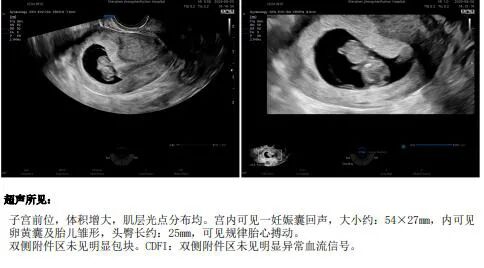

2025年7月顺利移植(1个囊胚),一次顺利好孕并“毕业”。

在生殖助孕中心的耿蔷主任团队的帮助下,魏女士终于迎来了好孕消息。